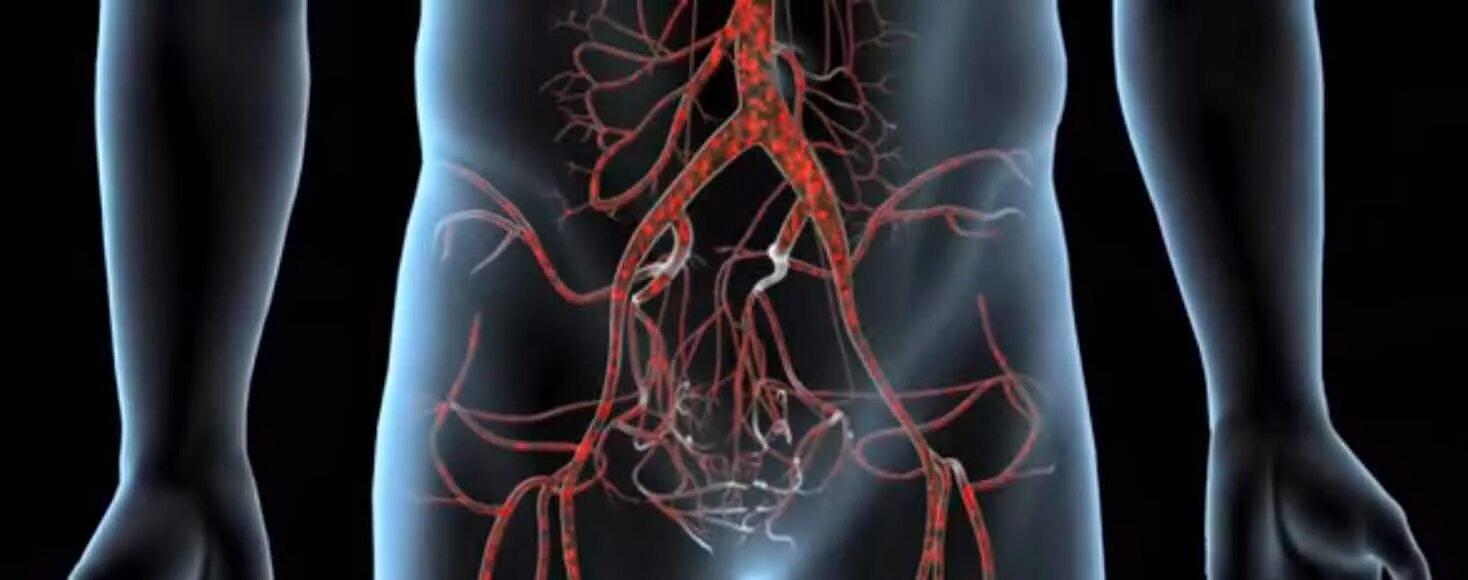

Тромбоз аневризмы аорты